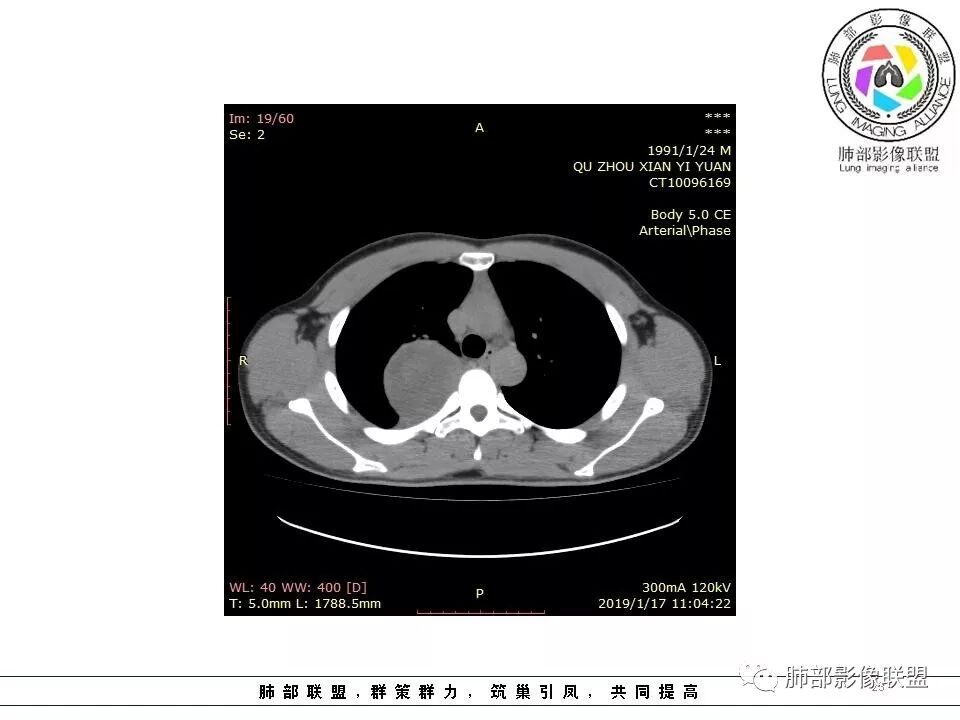

脏层胸膜主要由支气管动脉和肺动脉供血,壁层胸膜主要由支气管动脉,胸廓内动脉、肋间动脉供血

如果是肋间动脉,就不可能是脏层胸膜,可以是壁层或者纵膈

但是这个病人,肋间动脉供血吧,我倾向胸膜

肋间动脉供血,强化尚均匀,逐步强化

供血,体外供血,体循环,要么是壁层胸膜,要么胸膜外的,脏层胸膜应该是对内供血。病变里面的血管,除非是非常粗大迂曲的血管,不然,我不认为是其特点。

脏层胸膜肺内供血,壁层胸膜体外供血

这个病人不是肺动脉与支气管动脉供血,是肋间动脉供血

2.肋间动脉病供血也提示肿块来自后纵隔?